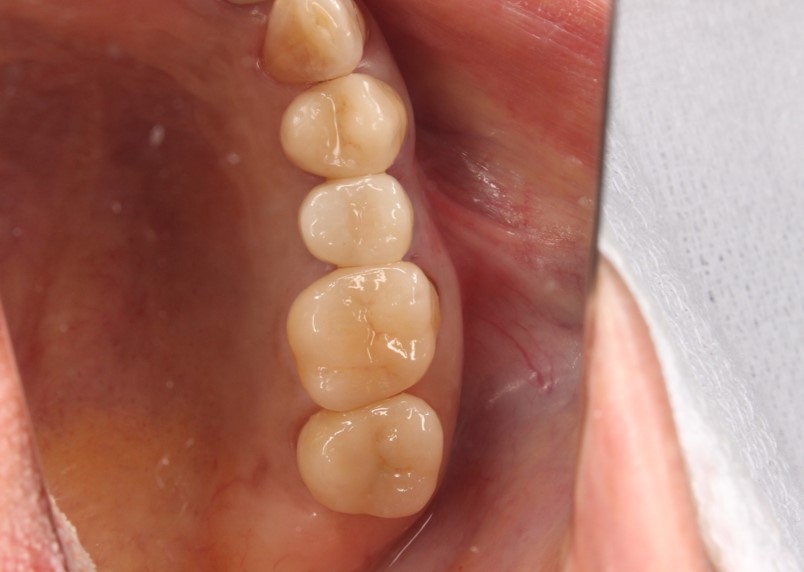

治療後

満足して頂きました。

まだ下の歯の治療(今後、型どりをして、インプラントの上部構造を製作予定)がありますが、少しずつ綺麗になっていく自分の歯について、うれしそうに話している姿が印象的でした。

インプラントの手前の歯は、根管治療を行いセラミックの被せ物をしました。

奥の歯2本は、それぞれ2次虫歯でしたが、神経は感染していなかったので、健康なエナメル質は温存して、セラミックとジルコニアで治療を行いました。